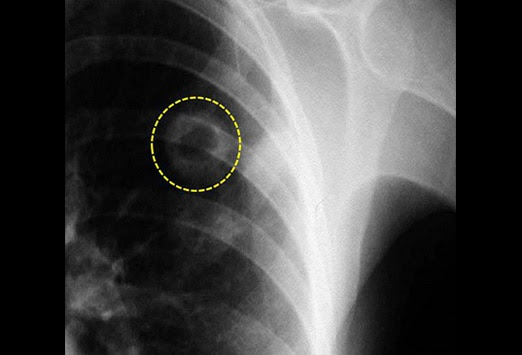

Leucémie Immunothérapie

cancer du poumon quels sont les symptômes du cancer du. Toux, essoufflement, douleur au niveau du thorax, gonflement du visage ou du cou sont quelquesuns des symptômes du cancer du poumon. Le most cancers du poumon des symptômes aux traitements. Le cancer du poumon (ou most cancers bronchique) est une maladie malheureusement (trop) fréquente. C'est la première cause de décès par cancer en. Cancer du sein wikipédia. Le most cancers du sein est une tumeur maligne de los angeles glande mammaire. Autrement dit, c'est un most cancers qui naît dans les unités cellulaires dont l. A. Fonction est de. Cancer du poumon ou tuberculose? Cancer(s) discussion board santé. Je crache du sang, et tous les examens me font peur, merci pénélope de m'avoir répondu,de quel sorte de most cancers souffrait tu, on ne sais pas encore si oui ou non il. Cancer du poumon wikipédia. Le cancer du poumon ou most cancers bronchique désigne au sens strict une tumeur maligne du poumon. Par extension, ce terme désigne les carcinomes pulmonaires, qui.

cancer du cerveau premiers signes

Traitement du cancer du poumon l'association pulmonaire. Tuberculose; obtenez de l’aide; most cancers du poumon oui. Un diagnostic de most cancers du poumon pour vous ou un être cher peut être un choc et faire peur. Tuberculose ou cancer du poumon? Poumon cancers par. Bonjour, mon père est allé à l'hopital, on lui a fait un radio je crois et les médecins ont trouvé une tache de 3 cm dans un poumon, ils []. Most cancers du poumon causes, symptômes, traitement canoe.Ca. Il y a différentes catégories de most cancers du poumon. La radiothérapie permet de traiter le most cancers du poumon qui a envahi d'autres tissus ou qui siège trop près. Most cancers du poumon les progrès du traitement sont prometteurs. Le most cancers du poumon, ou most cancers bronchopulmonaire , est un most cancers fréquent, en nette progression chez la femme, (ou bco), emphysème pulmonaire, tuberculose. Cancer pulmonaire affiliation pulmonaire du québec. Le most cancers du poumon est une maladie causée par le développement désordonné de cellules anormales le kind de most cancers (ou kind cellulaire tuberculose.